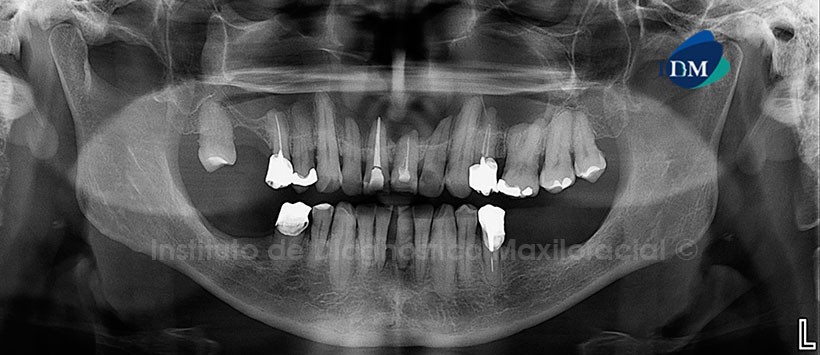

A la evaluación de la radiografía panorámica  se aprecia perdida de piezas dentarías en ambos maxilares y reabsorción ósea moderada del maxilar inferior, múltiples restauraciones, material de obturación de conducto en las piezas 15, 11, 21 (sobrextendida), 24 y 35 así como la presencia de espigo metálico en piezas 25, 24 y 34 además de coronas protésicas en la pieza 45 y las piezas mencionadas previamente.

Siendo lo más resaltante la presencia de una imagen radiolucida, localizada en la zona nasomaxilar que se extiende desde mesial de la pieza 18 hasta mesial de la pieza 27, de limites parcialmente definidos y parcialmente corticalizados, así mismo se evidencia un borramiento del hueso medular, laminas duras, piso de seno maxilar y fosa nasal así como reabsorciones leves a nivel periapical de las piezas 21 y 22.(Figura 1)